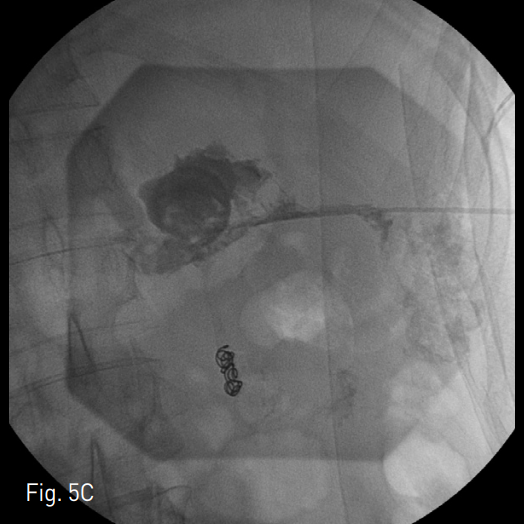

초음파 유도하에 왼쪽 측와위에서 췌장 미부 주위 액체 저류를 조준하여 22 gauge Chiba needle로 천자하였음. 조영제를 주입하여 액체 저류 안에 들어온 것을 확인하고 차례로 확장기를 진입시킨 후 18 Fr Thal-Quick chest tube (Cook, Bloomington, IN,USA)를 거치하였음 (Fig. 2). 이후 냄새가 나는 연갈색의 농이 배액되어, 카테터를 배액용기에 연결한 후 시술을 종료 함. 이후 2개월간 11번 동안 혈관조영실을 방문하여 평균 8000cc정도의 생리 식염수를 이용한 적극적인 세척과 함께 50cc 관장용 주사기로 흡인하여 괴사 제거술을 시행하였음 (Fig. 3). 출혈을 피하기 위해, 괴사 제거술은 흡인으로 쉽게 제거되는 괴사물 정도에 대해서만 국한하여 시행하였으며, 과도한 유도철사의 움직임은 최소화하였음. 흡인물에서 육안으로 신선 혈액이 확인되는 경우는 바로 시술을 종료하였음. 2개월 뒤 추적 전산화 단층촬영술 축상면 영상에서 삽입되어 있는 도관과 함께 주변 괴사 조직과 액체 저류가 양이 매우 감소한 것을 확인하였음 (Fig. 4). 당시에도 거짓동맥류 등의 중요 합병증은 보이지 않았음. 이에 14 Fr MSL catheter (Cook, Bloomington, IN, USA)로 교체하여 배액을 마무리하기로 하였음. 이후 조영제를 주입하였을 때 소장과의 샛길이 보였고 통제된 샛길 (controlled fistula)를 형성하기 위해 1주일간 카테터를 유지하기로 하였음. 1주일 뒤에 환자 이전의 발열 및 복통 증상이 호전되어 다시 악화되지 않음을 확인한 후 유도철사와 5 Fr KMP catheter (Cook, Bloomin gton, IN, USA)를 이용하여 샛길의 경로를 조영제로 확인하고 4mm MicroNester (Cook, Bloomington, IN,USA)와 Histoacryl (B. Braun, Melsungen, Germany),

Lipiodol Ultra Fluride (Guerbet, Roissy, France)의 혼합물을 이용하여 색전술을 시행하였음. 이후 조영제를 주입하였을 때 더 이상 소장으로의 샛길은 보이지 않아 Nelaton catheter를 이전의 삽입경로에 일시적으로 거치한 후 시술을 종료하였음 (Fig. 5).

Fig. 5

Fistula between fluid cavity and jejunum was noted (A). Successful navigation to fistula tract was done with 0.035inch hydrophilic guide wire and 5 Fr KMP catheter (Cook, Bloomington, IN, USA) (B). Controlled fistula tract was embolized with 4mm Tornado (Cook, Blooming ton, IN, USA) and Histoacryl (B. Braun, Melsungen, Germany), Lipiodol Ultra Fluride (Guerbet, Roissy, France) mixture. Post-embolization tubogram showed no demonstation of previous fistula. Nelaton catheter was deployed to formation of con trolled fistula (C). 1 week later, bedside removal of Nelaton catheter was done.